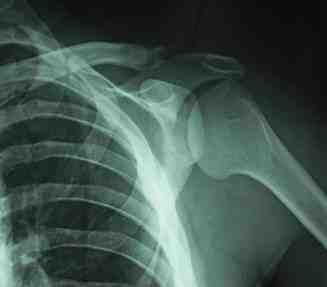

Paciente varón de 30 años de edad que sufrió una luxación acromioclavicular izquierda tipo III de la clasificación de Rockwood y Matsen (Fig. 1) siendo intervenido hace un año mediante reducción y fijación transarticular con dos agujas de Kirschner. El paciente acudió a consulta para revisión postquirúrgica. No destacaban otros antecedentes personales de interés. Antes de la lesión, la actividad basal del paciente era normal para su edad. No seguía tratamiento crónico salvo la toma de analgésicos ocasionalmente. En la exploración física destacaba la presencia de deformidad y dolor a la palpación en la articulación acromio-clavicular izquierda, que le limitaba en sus actividades habituales diarias. No se objetivaron alteraciones vasculonerviosas a nivel distal.

Figura 1. La radiografía simple anteroposterior de hombro izquierdo antes de la primera cirugía (en el momento agudo) que mostraba una luxación acromioclavicular tipo III de Rockwood y Matsen.